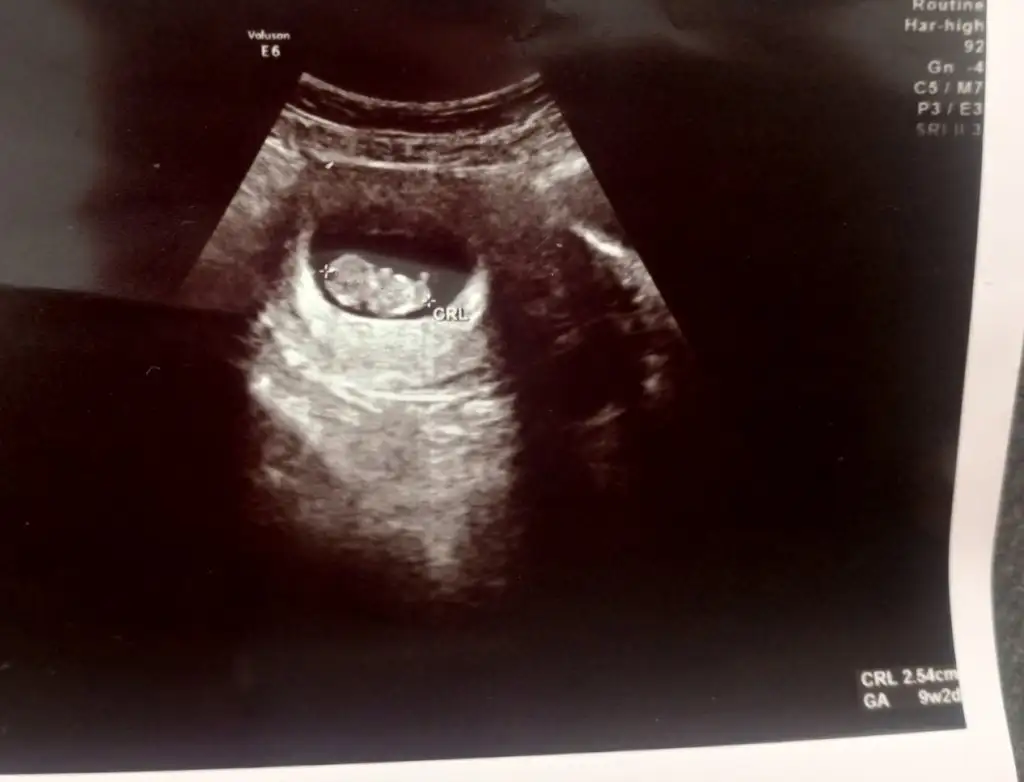

Ayyy ne güzel ya ben en son 7. Haftada gittim çok derinden bi kalp atışı duyduk yarın 9. Haftam doktora gideceğiz eğer güçlü kalp atışı duyarsam ben de bişeyler almak istiyorumMerhabaa kızlar eklemeleri birazdan yapıcam eşimi işe göndermeyi bekliyorumDün biz tekrar bebişi gördük 9+2ydi ultrasonda ve biraz dayanamayıp minik bir alışveriş yaptımmm